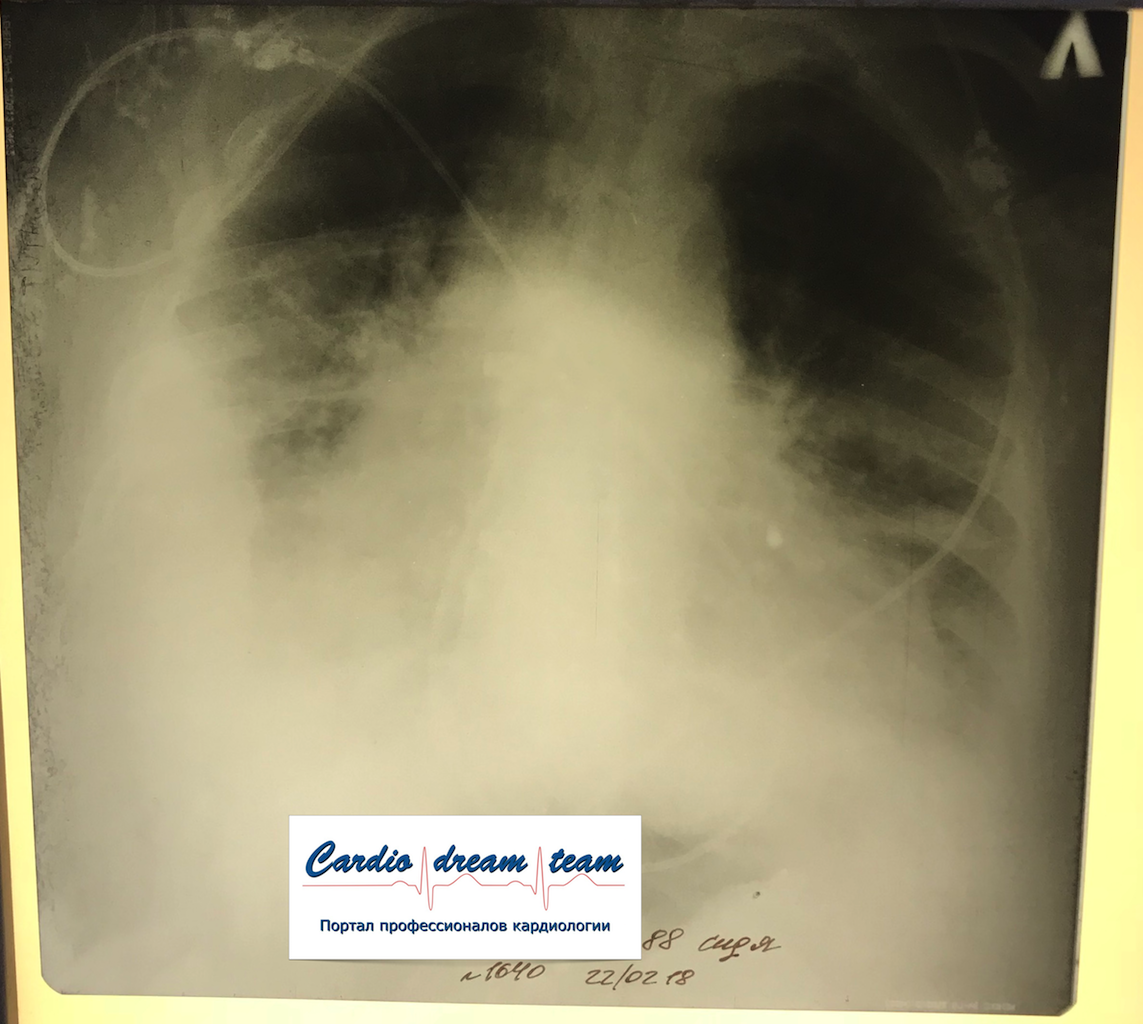

Правосторонний осумкованный гидроторакс.